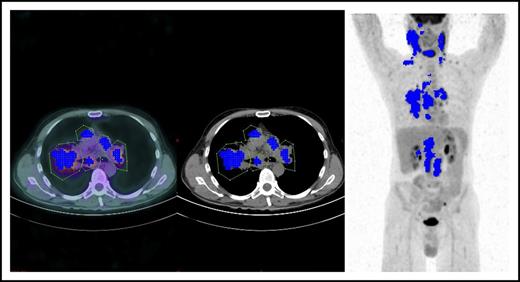

Tumor segmentation in an HL patient showing 5 sizeable mediastinal lymph nodes (courtesy of Salim Kanoun).

MTV is one of the most promising applications of quantitative FDG-PET scan (QPET) reading.8 FDG-PET is indeed an intrinsically quantitative imaging tool capable, in theory, of detecting and measuring all the voxels contained within the tumor, thus portraying, in a single shot, the overall functionally active tumor burden. The QPET readout consists of a computer-assisted mathematical calculation of numerical variables, such as MTV and total lesion glycolysis, moving from a unit of measure, the standardized uptake value (SUV), which is the ratio between the measured activity and the injected activity per voxel, normalized to body surface area. After manual contouring of every single tumor mass, the algorithm to compute MTV starts with tumor segmentation, that is, the decomposition in a 3-dimensional space of every Voxel measured within a contoured tumor mass showing an SUV value between the SUV maximum (SUVmax) and the SUV threshold (see figure). The latter could be a fixed percentage of SUVmax, for instance, 41% as in the Moskowitz et al article, or an absolute value. Thus, QPET could achieve 2 ambitious goals at the same time: (1) providing a partially operator-independent PET scan reading, and (2) transforming a descriptive imaging report into a number, as in other prognostic biochemical markers. However, several hurdles still preclude the use of bMTV as a reliable and reproducible biomarker in clinical practice, as recently pointed out by the same authors of the article.9 As a matter of fact, a number of biological and physical factors as well as technical errors could undermine the absolute SUV measurement, with variability ranging between 15% and 75% when this value is obtained from different PET scanners with different hardware in multicenter trials.10 Nonetheless, several newer experiences have been published, demonstrating that this variability could be decreased if the procedure for PET scanning is harmonized among sites and if PET/CT scanners are intercalibrated. Moreover, a debate still exists on the threshold to be used in SUVmax measurement and on the best segmentation algorithm. Because it is not possible to evaluate, from a methodological point of view, the accuracy in tumor delineation of the single segmentation algorithm, a plethora of them have been used to determine MTV with different results. Finally, MTV behaves as a continuous nonlinear variable, and therefore a number of different cut-off values to predict treatment outcome have been proposed so far, making it useless for clinical purposes. As a matter of fact, the bMTV prognostic role has so far only been demonstrated in retrospective studies or single-center studies, in which the abovementioned methodological flaws are bypassed or minimized. Therefore, prospective studies with calibrated scanners with homogeneous hardware equipment adopting the same software for MTV computing and the same SUV threshold are urgently needed.